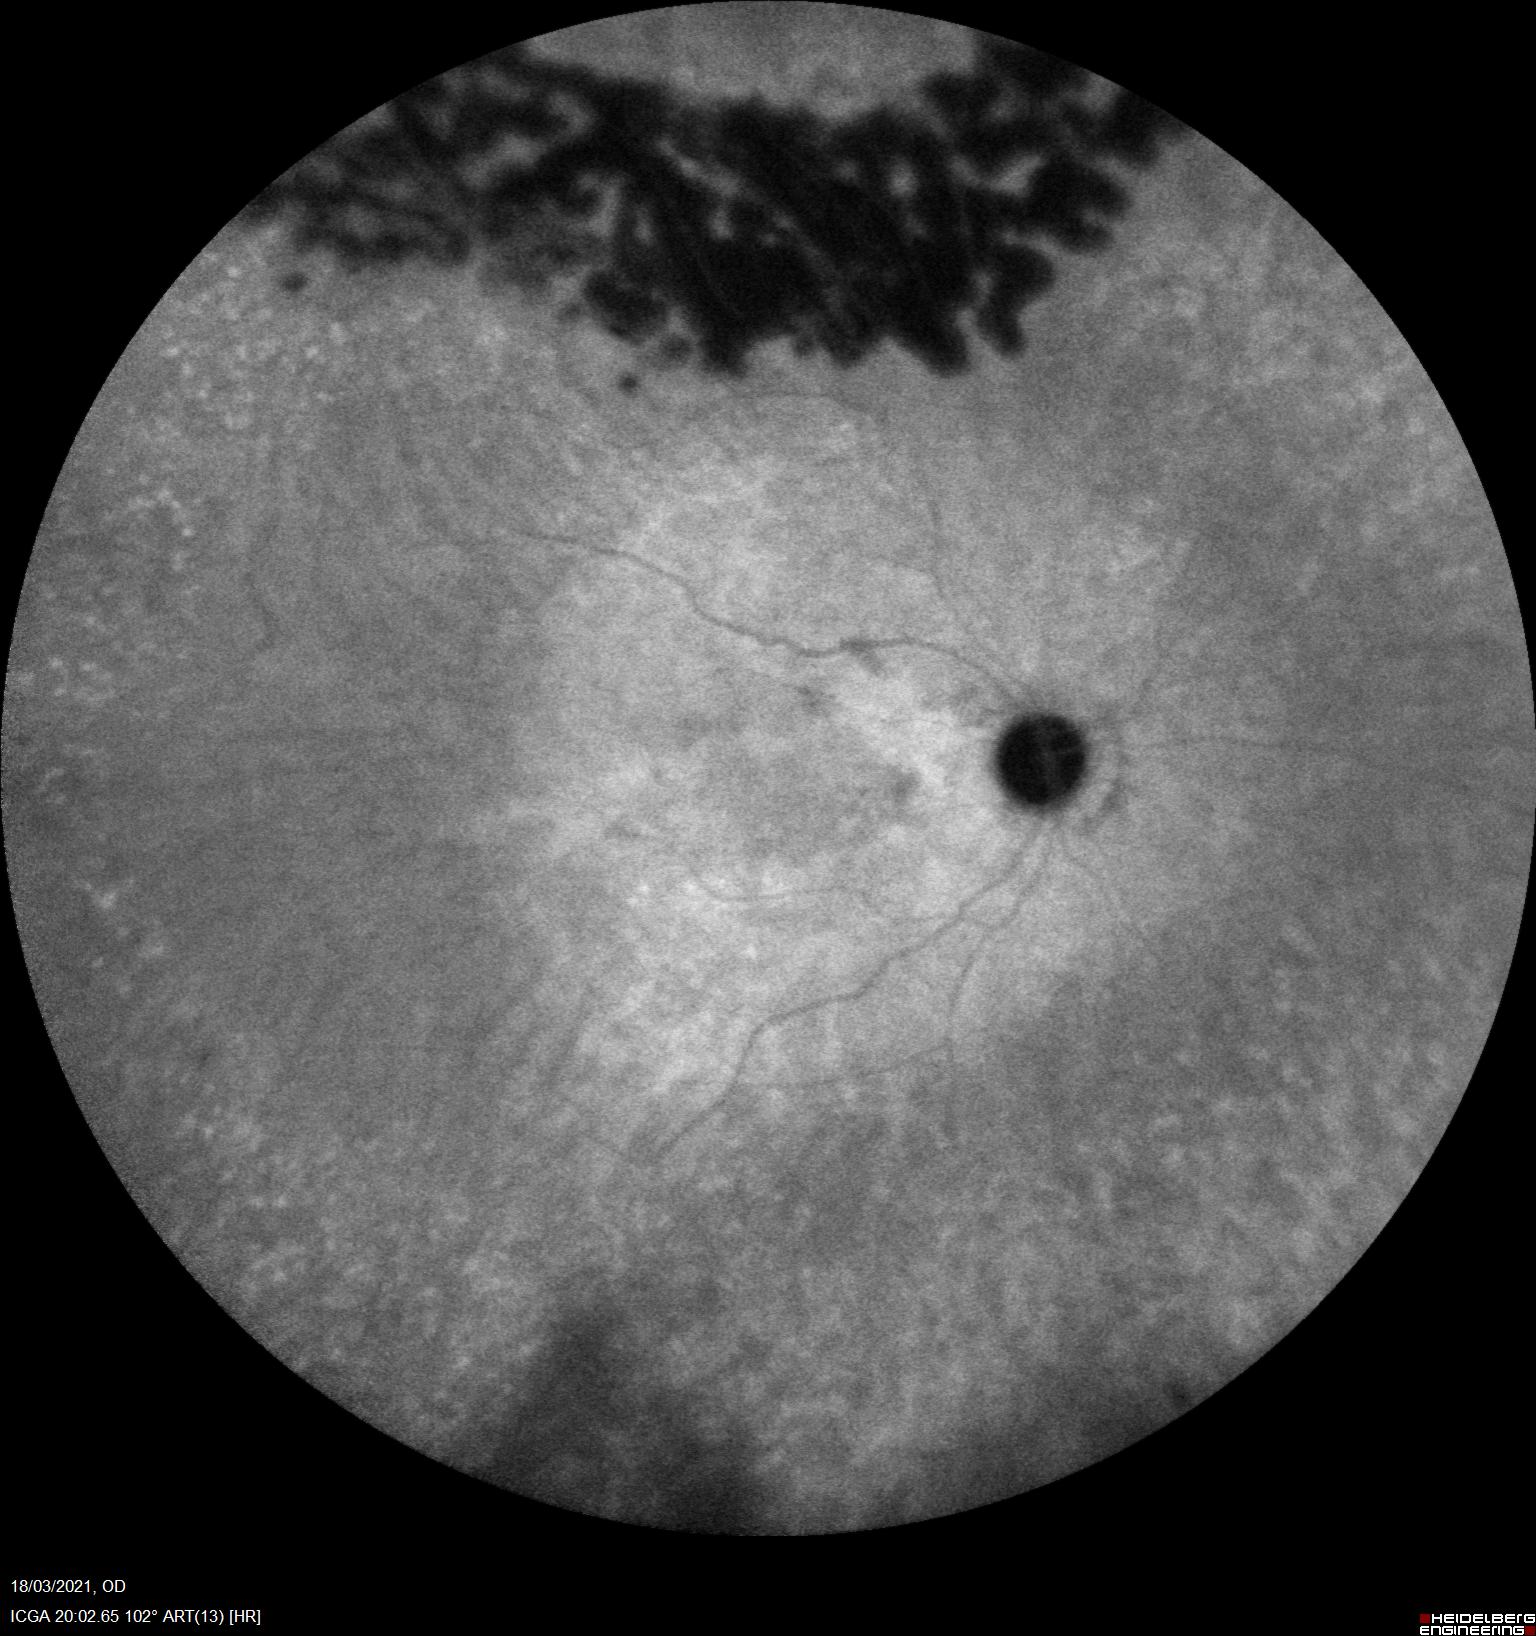

Una de las herramientas más útiles para su diagnóstico es la angiografía con verde de indocianina.

En la ICV podemos apreciar una hipercianescencia precoz con una iso/hipocianescencia tardía que refleja el alto flujo vascular y capacidad de lavado que presentan estos tumores vasculares a diferencia de otros funduscopicamente similares.